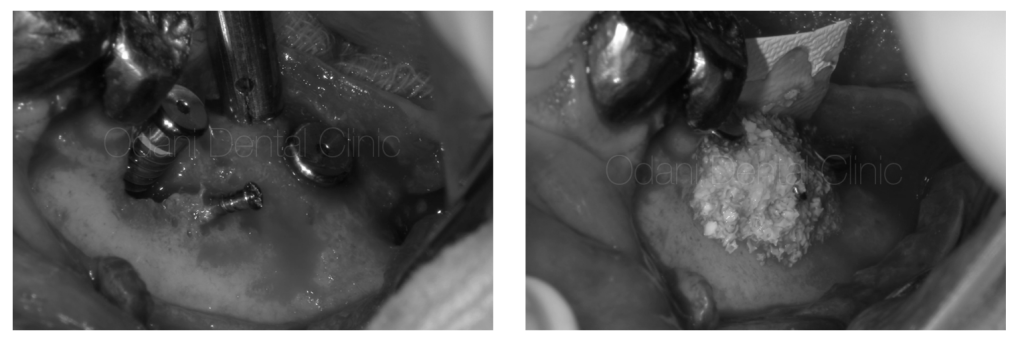

一次手術(インプラント埋入+骨造成)

事前のCT画像によるシミュレーション通り、インプラント体を埋入するとインプラントのネジが大きく露出した状態(左写真)です。骨を作りたいところにチタン性のピンをテントの支柱のようなイメージで植立し、骨移植材を用いて骨造成を図りました(右写真)。